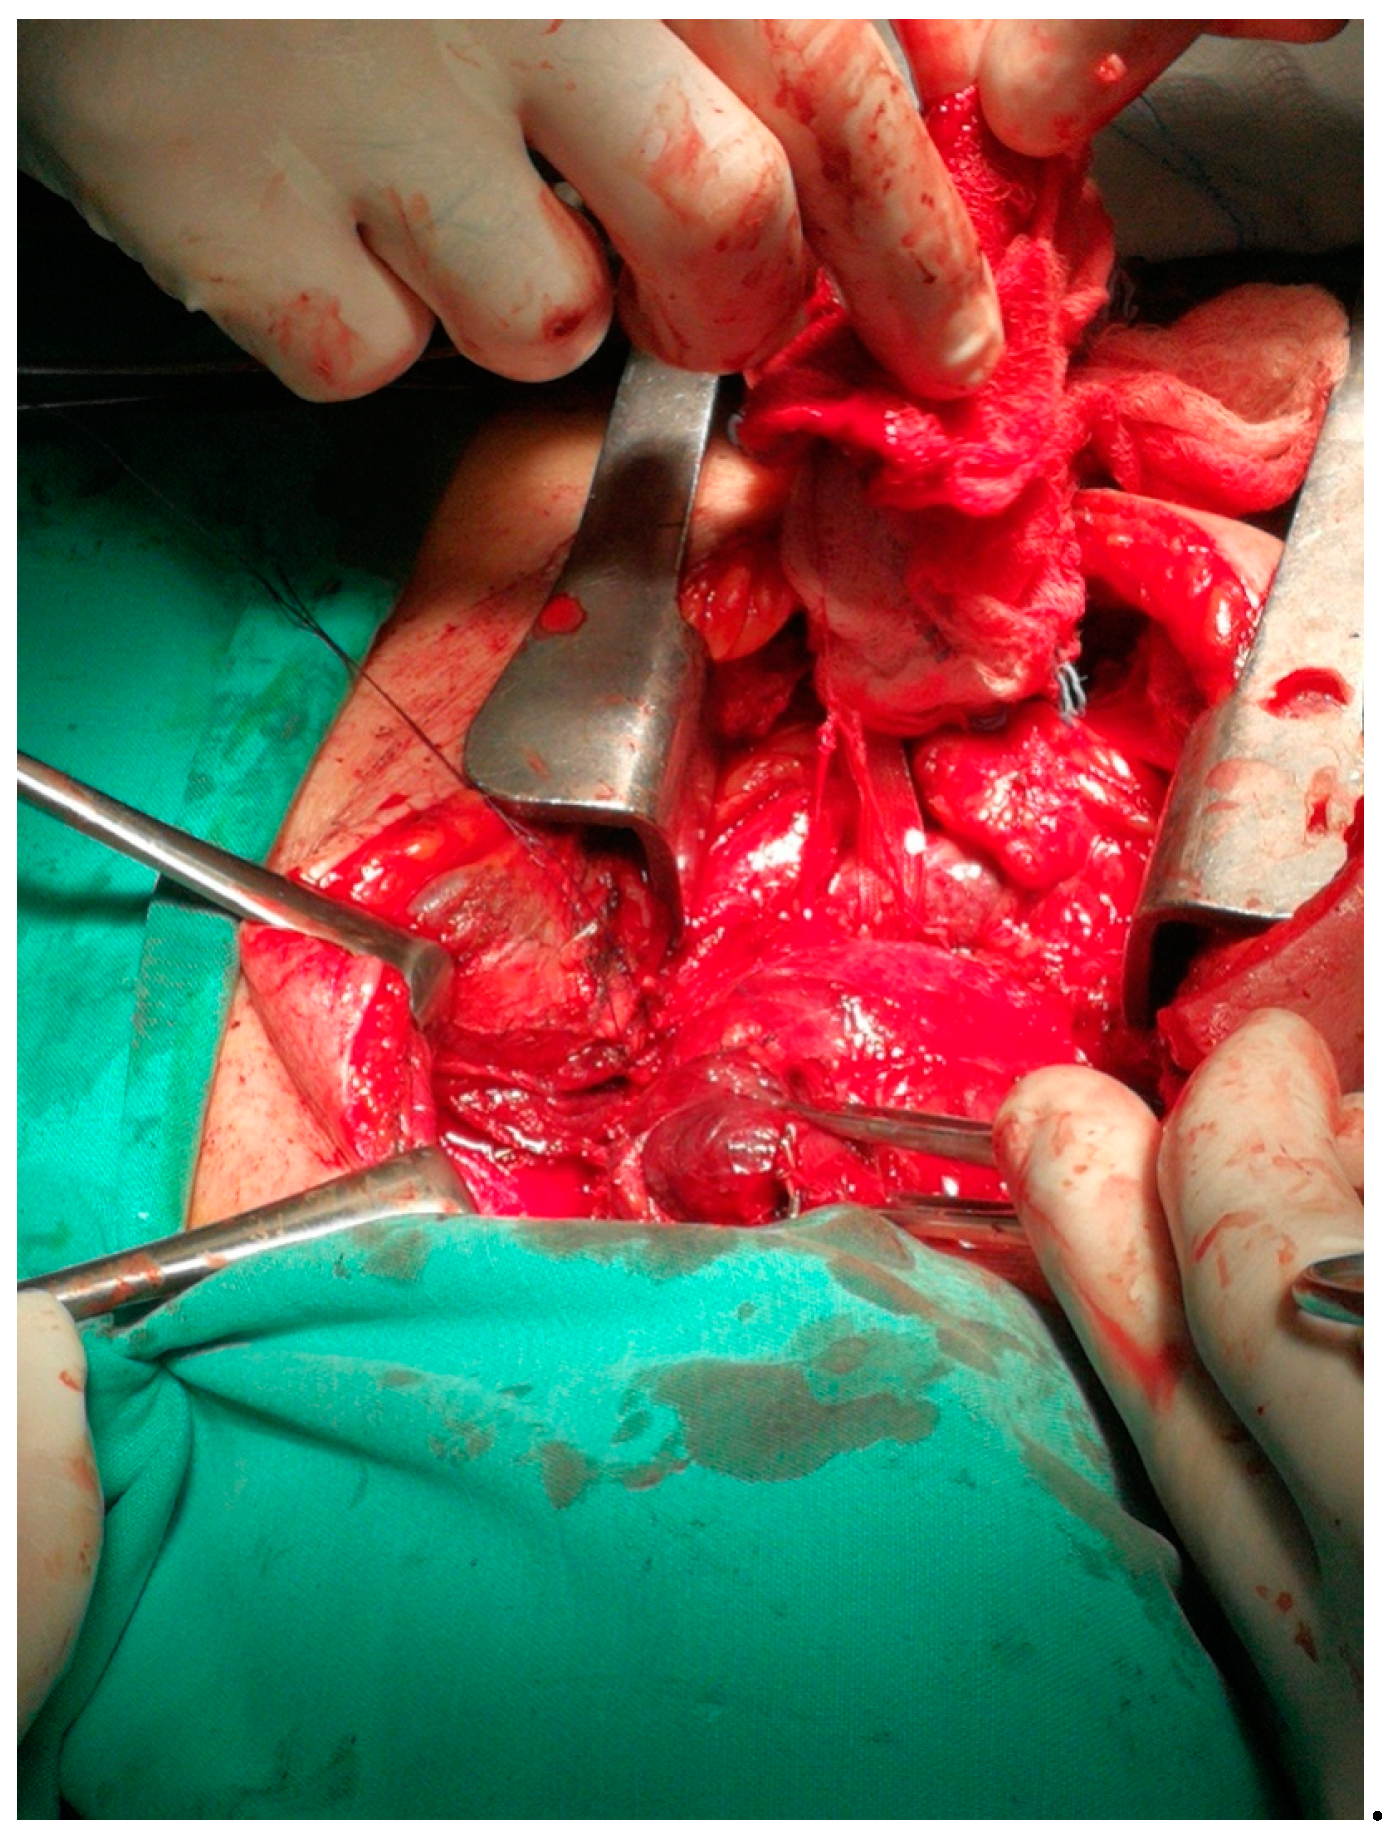

Cardiopulmonary Arrest Caused by Large Substernal Goiter—Treatment with Combined Cervical Approach and Median Mini-Sternotomy: Report of a Case

Koulouris, C.; Paraschou, A.; Manaki, V.; Mantalovas, S.; Spiridou, K.; Spiridou, A.; Laskou, S.; Michalopoulos, N.; Radu, P.A.; Cartu, D.; et al. Cardiopulmonary Arrest Caused by Large Substernal Goiter—Treatment with Combined Cervical Approach and Median Mini-Sternotomy: Report of a Case. Medicina 2021, 57, 303. https://doi.org/10.3390/medicina57040303